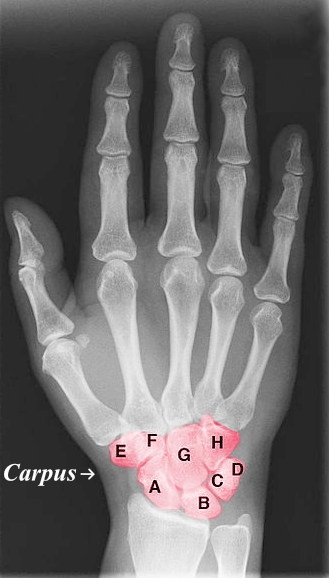

Letter A

Scaphoid

Letter B

Lunate

Letter C

Triquetrum

Letter D

Pisiform

Letter E

Trapezium

Letter F

Trapezoid

Letter G

Capitate

Letter H

Hamate

Purple Area

Carpus